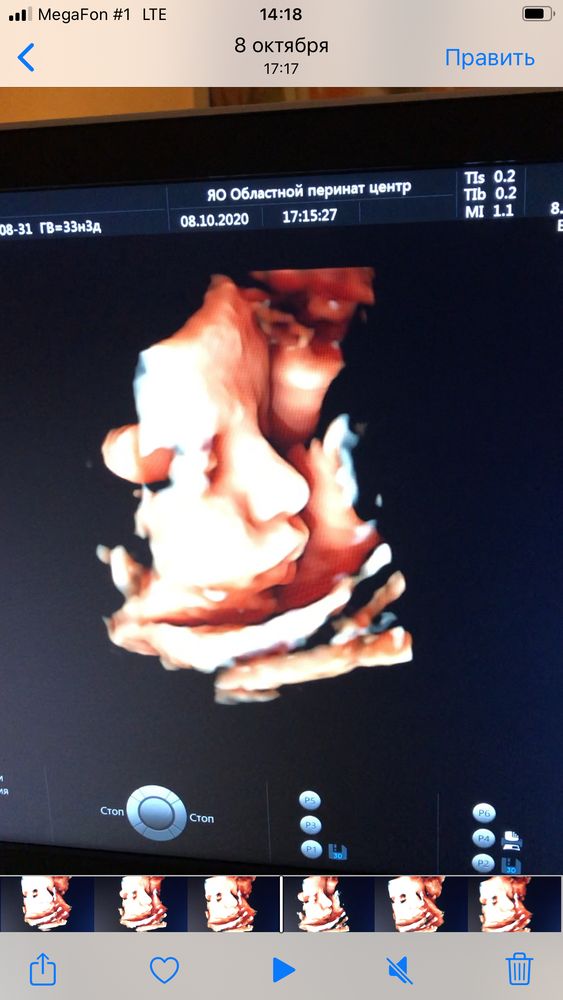

вот в 34 ещё делали)) Обычно все детки поджимают нижнюю губу,наш наоборот,выпячивает 😀ой,я так рада была,когда увидела его губы))) у мужа пухлые,красивые,как раз хотела,чтобы как у мужа были))

20.10.2020